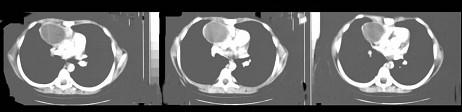

问题 14岁,男,胸闷咳嗽一个月,曾咳出过毛发,CT检查如图,请选择最可能的诊断 ( )

选项 A、畸胎瘤 B、食管囊肿 C、胸内甲状腺肿 D、胸腺囊肿 E、纵隔血肿

答案 A